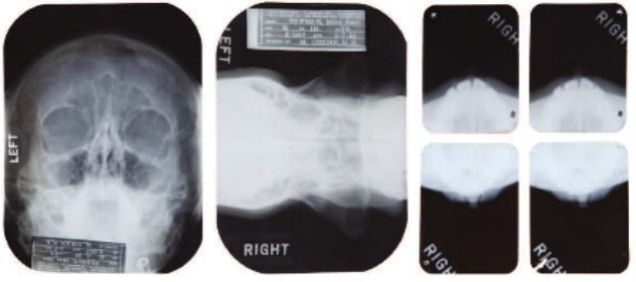

Monroe's medical files sold for $25,600, so if you were ever hoping to own an X-ray of the innermost reaches of the bombshell's skull, you're out of luck for now. The files, which come from the last five years of her life, don't actually refer to the star by name. But they're definitely not fakes: one of several undercover aliases Monroe used for her doctor visits matches up with her final home address, and her psychoanalyst is mentioned by name.

Although the records don't show what one might typically think of as Monroe's most intimate parts, they do illuminate and confirm rumors about her life. In addition to lists of personal insecurities and referrals from the psychoanalyst's log, the lot includes records of an immune deficiency issue, an ectopic pregnancy, and—the moment you've all been waiting for—confirmation of plastic surgery. It's kind of gross, though: the record in question features "a note that a 1950 chin implant involving a tip rhinoplasty procedure was dissolving."

[image via Julien's Auctions]